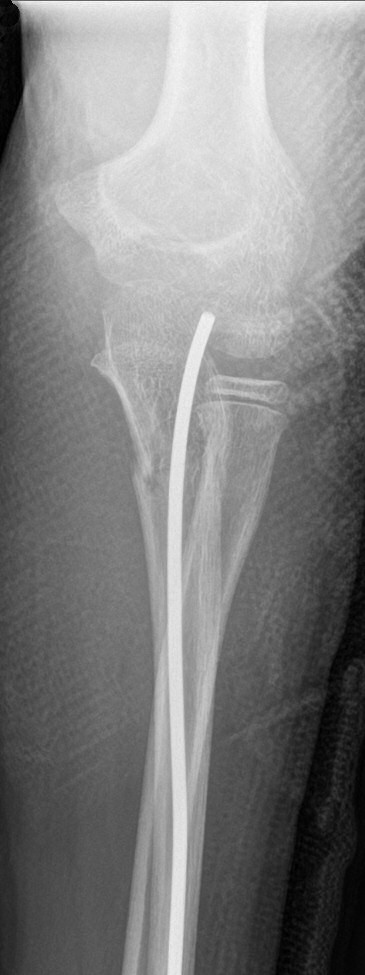

Monteggiafraktur: fraktur på ulna och samtidig luxation av caput radii. Man är inte helt överens om ulnafrakturen ska vara i den proximala tredjedelen [2] eller proximala två tredjedelarna av ulna [3]. Radiushuvudet kan också vara frakturerat istället för luxerat [2].

Monteggiafraktur, opererad med TEN-spik